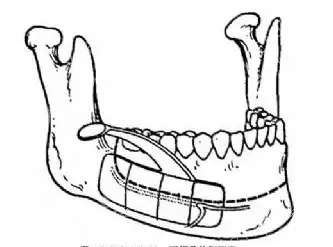

面诊那天,罗医生拿CT片给我看:“你的下颌骨过度前突,单纯正畸结果有限,双颚手术调整上下颌骨位置,才能根本解决问题。”他说话很慢,每个术语都用“下巴往前跑”“牙齿咬不齐”这种我能听懂的词解释,诊室墙上挂着2018年的患者术后对比照,现在还能找到那位姐姐的小红书账号——这让我踏实了。

手术前三天要做牙模、拍3D CT,连牙齿咬合关系都要正确到毫米。进手术室那天我紧张得手抖,护士姐姐握着我的手涂碘伏:“我们罗管理者做这种手术十多年了,手法特别稳,你睡一觉就好。”

麻醉师问我“数到10”,数到7就没意识了。后来看手术记录,整个过程2小时15分钟,罗医生团队用小切口操作,尽量避开神经和血管——这也是我术后肿胀比小琪轻的原因。